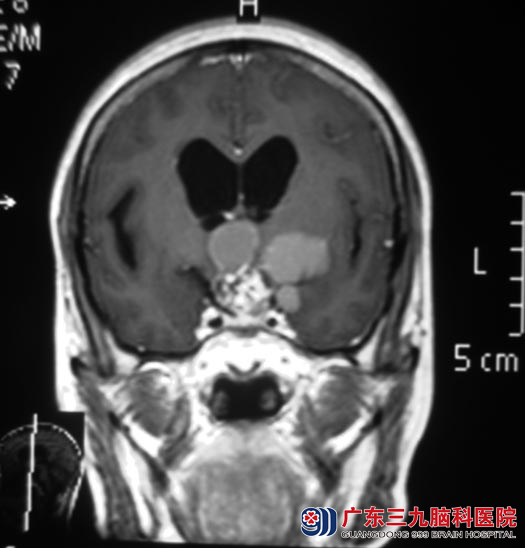

头颅MR检查提示:鞍上与鞍旁左侧示一不规则形状囊实性占位性病变,大小约45.5mm×32.1mm×35.8mm,考虑颅咽管瘤,中度脑积水。

完善相关检查后,由鲁明主任主刀,在全麻下行鞍区颅咽管瘤切除术,术中见囊实性黄白色肿瘤组织位于鞍区向鞍上生长,显微镜下分块切除肿瘤,肿瘤包绕双侧颈内动脉及其分支、与垂体柄粘连紧密,小心予以分离、切除,垂体柄保留完整,手术顺利。术后李阿姨的头痛、呕吐症状均得到改善,已康复出院。术后病理结果:颅咽管瘤。